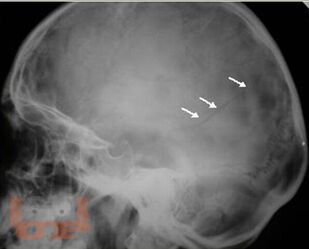

В учебном пособии представлены современные взгляды на вопросы этиологии, патогенеза, диагностики и оперативного лечения черепно-мозговой травмы у детей.